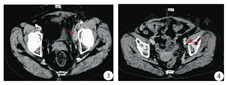

患者女,66岁,因左下肢水肿2月余,2009年6月于汉中市中心医院就诊。患者无腰痛、尿少、血尿、尿痛、尿急、发热、腹痛、腹泻、腹胀、下肢疼痛不适等症状。曾在当地医院检查肾功能未见异常,未治疗。患者左下肢水肿逐渐加重,伴有活动不适及隐痛。查体:体温36.8℃,浅表淋巴结未触及肿大,心肺无异常;腹部稍膨隆,未见腹壁静脉曲张,未见胃肠型和蠕动波,腹部无压痛及反跳痛,腹部未扪及包块。肝脾肋下未触及,肝肾区无叩击痛,移动性浊音阴性,肠鸣音正常。左下肢明显水肿,无溃烂及渗液,皮肤温度及活动正常。肛门指诊:黏膜光滑,未触及肿块,指套染黄色粪迹。实验室检查:血常规、尿常规、肝功、肾功、电解质、血脂等均正常。入院后盆腔增强CT显示左侧盆腔可见4.3 cm×2.4 cm混杂低密度影包绕髂外动脉,与血管间界限不清(图1),考虑肿瘤占位。考虑左髂静脉受肿瘤侵犯致管腔狭窄静脉血回流不畅所致,予行血管造影证实(图2)。盆腔肿块穿刺病理检查:可能为软组织黄色肉芽肿。手术探查术中见腹内无腹水,肝、胆囊、脾、大小网膜、小肠及其系膜、结肠及其系膜表面,胃前壁腹膜等腹内脏器未见明显肿瘤转移结节,腹主动脉旁及肠系膜上血管根部无肿大淋巴结。肿瘤位于左侧盆腔侧后壁,大小为10.0 cm×5.0 cm×2.0 cm,不规则,肿块质地硬,固定,边界不清,包裹髂内动静脉,肿块固定无法切除。术中肿块穿刺活检示:可见大量肿瘤细胞呈泡沫样,细胞间有纤维组织和血管增生,有较多异型的上皮细胞和梭形细胞。病理诊断为黄色肉芽肿。术后16 d行三维立体适型放射治疗,设四野照射,照射剂量为PCTV:2 Gy/次,5次/周,连续5周。2009年8月初放射治疗结束后,复查盆腔CT显示:左侧髂窝肿块较前缩小,病变大小约为2.1 cm×1.8 cm(图3)。Recist标准疗效评级部分缓解。6个月后,左下肢水肿逐渐消退,复查盆腔CT显示:左侧髂窝肿块较前无增大,遂植入血管扩张支架1枚,左下肢水肿逐渐完全消退,并多次复查盆腔CT,2017年10月初CT提示病灶仍稳定,左侧髂窝肿块完全消退,并可见金属支架影(图4)。3~6个月复查1次,目前已随访8年余,病情稳定,患者生活完全能自理,继续随访中。